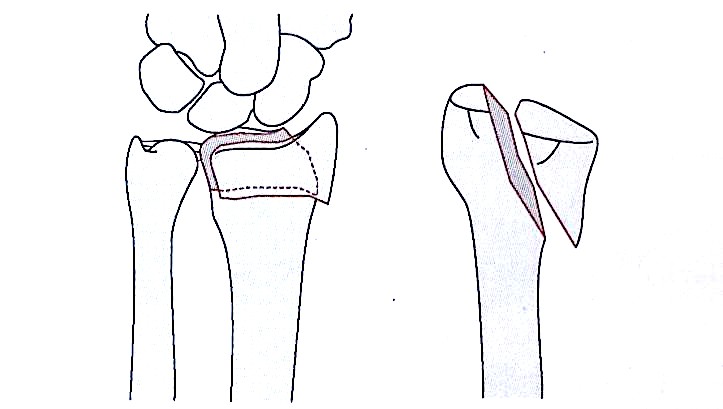

Metafizni fleksijski zlom tipa I

Sklepni in strižni zlom tipa II

Kompresijski zlom sklepne površine tipa III

Tip IV avulzijski zlom radialnega zapestja, izpah

Mešani zlomi tipa V (visokoenergijski avulzijski zlomi)